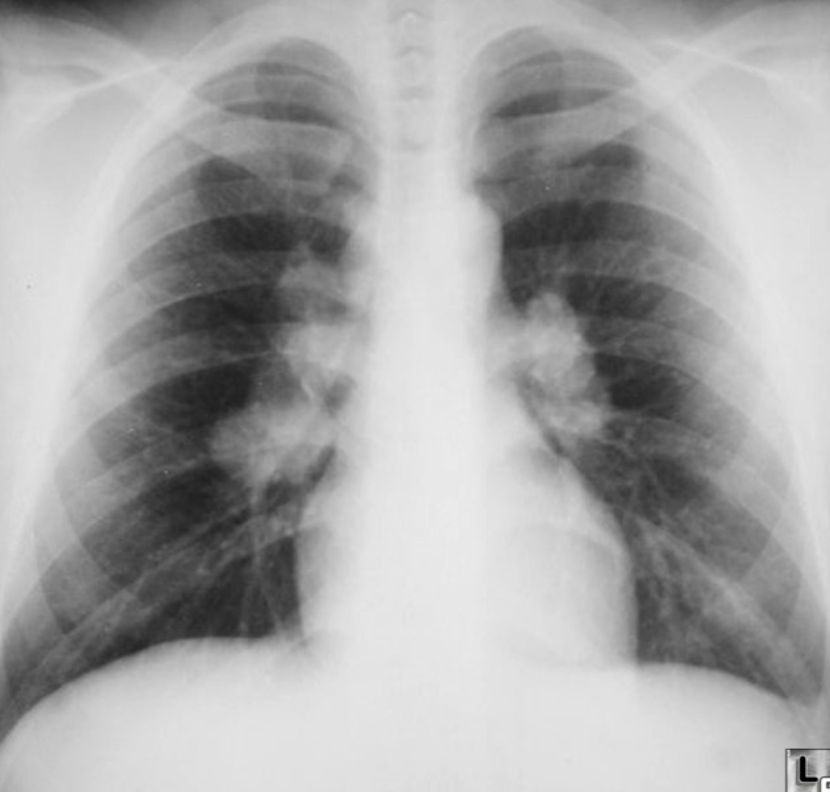

Patient with recurrent attacks of dyspnea and chest tightness after exercise. Clinical diagnosis bronchial asthma. Chest X ray is as follows:

Q1: in this chest x-ray normal or abnormal? Normal.

Q2: on chest auscultation, what added sounds can be heard in asthma? Wheeze.

Q3: Name any drug which can precipitate asthma? NSAIDS, Beta blockers.

Q4: You ordered spirometry for this pt. what will be the expected finding? FEV1 is reduced.

Q5: Name 2 clinical features of severe asthma? Z Can Not complete a sentence in one breath, Tachypnea, cyanosis

Q6: What ttt will you give in moderate to severe asthma? Name any 2. Bronchodilators, corticosteroids.